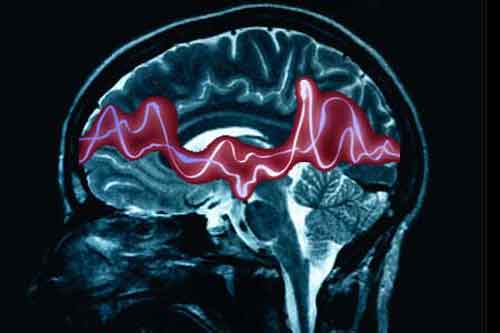

Precedenti studi di imaging su pazienti con epilessia del lobo temporale hanno mostrato anomalie nella struttura del cervello, in particolare nell’ippocampo, nel talamo, in altre strutture sottocorticali e nel volume della materia bianca. Tuttavia, vi e’ una scarsa conoscenza degli effetti dell’invecchiamento su questi cambiamenti cerebrali strutturali. Per caratterizzare e correlare all’eta’ le differenze incorse nella struttura del cervello, Bruce Her mann e i colleghi della University of Wisconsin-Madison hanno reclutato 55 pazienti con infezione cronica da epilessia del lobo temporale, comparandole con un campione di controllo di 53 persone sane. I partecipanti avevano in media tra i 14 e i 60 anni. La risonanza magnetica (MRI) e’ stata utilizzata per misurare lo spessore corticale, l’area e il volume nel cervello di tutti i soggetti. Tra le altre cose, i ricercatori hanno scoperto che con l’avanzare dell’eta’ sia i soggetti con epilessia sia i soggetti sani presentavano cambiamenti progressivi nelle regioni corticali, sottocorticali e cerebellari, solo che i pazienti con epilessia mostravano anomalie piu’ estese. In particolare, nei pazienti affetti da epilessia si e’ registrata un’espansione molto piu’ marcata dei ventricoli laterali del cervello.